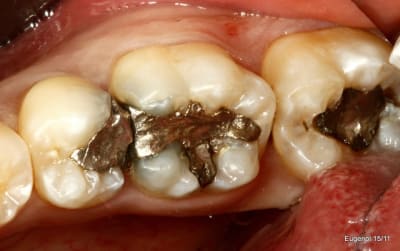

un truc que je fais souvent, quand je monte deux compo volumineux en contact, je monte le plus gros et difficile sans matrice et comme ça j'ai accès a la marge, et je peux donner une jolie forme galbée proximale

puis je monte le suivant avec une seule matrice...

plus facile je trouve d'avoir le point de contact